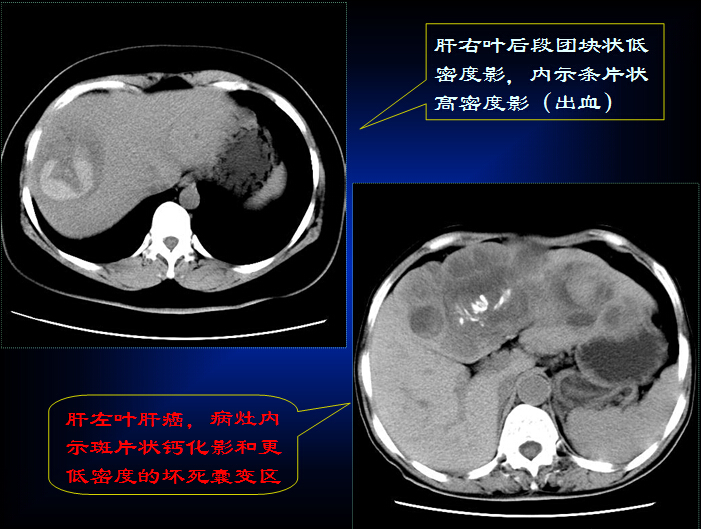

原发性肝癌的CT诊断